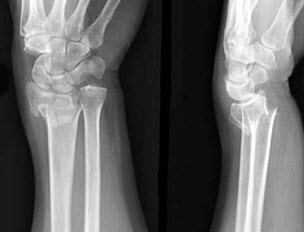

136、单项选择题

有外伤史,结合图像,最可能诊断是()

A.Smith骨折

B.尺骨骨折

C.未见异常

D.Colles骨折

E.腕关节脱位